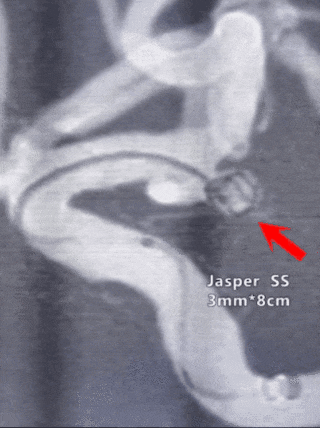

栓塞过程

经微导管送入第一枚Jasper®SS弹簧圈,可见弹簧圈十分柔软,瘤体及瘤颈成篮满意。后送入Jasper®SS弹簧圈,微导管给予一定张力后,头端摆动良好,无明显踢管现象,瘤体栓塞满意。

本病例难点在于大脑前动脉A1段起始处动脉瘤解剖位置刁钻,对微导管塑形及到位、弹簧圈的柔软程度和寻空能力有较高要求。Jasper®SS弹簧圈柔软度较高,踢管现象不明显,寻空能力较强,也是本病例成功单纯栓塞的基础。